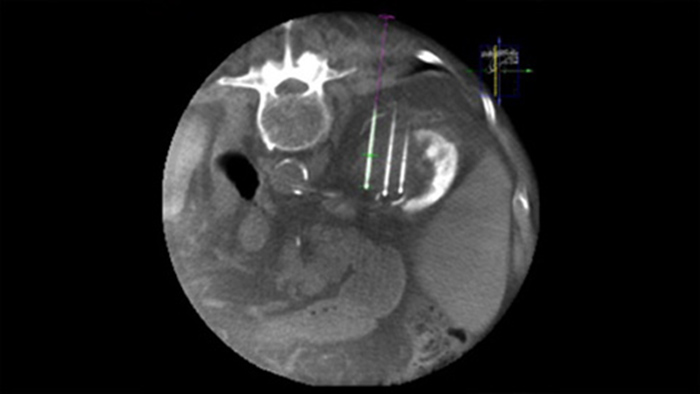

SmartCT Soft Tissue ofrece una técnica de adquisición de CT de haz cónico (CBCT) aumentada con guía paso a paso, visualización 3D avanzada y herramientas de medición; todas en el módulo de pantalla táctil de la mesa.

Dual View permite la superposición de una imagen 3D previa al procedimiento (TC/RM/PET-CT) en una CBCT Dual 3D durante procedimiento para visualizar mejor las lesiones y acceder a la entrada crítica para la planificación de la aguja.

La ablación percutánea (radiofrecuencia, microondas y crioablación) es un tratamiento mínimamente invasivo de eficacia comprobada de tumores renales, hepáticos, pulmonares y óseos. Es fundamental definir los límites del tumor y decidir un número óptimo de agujas y la trayectoria de la aguja correspondiente para poder realizar un tratamiento tumoral completo y no causar daños en el tejido circundante. Navegar con precisión en dosis bajas hacia la lesión de interés sin necesidad de cambiar la posición de la aguja aumenta la oportunidad de éxito y reduce el riesgo de complicaciones en las biopsias o ablaciones. La confirmación del criterio de valoración del tratamiento de ablación se puede lograr con imágenes 3D mientras el paciente aún se encuentra en la mesa.